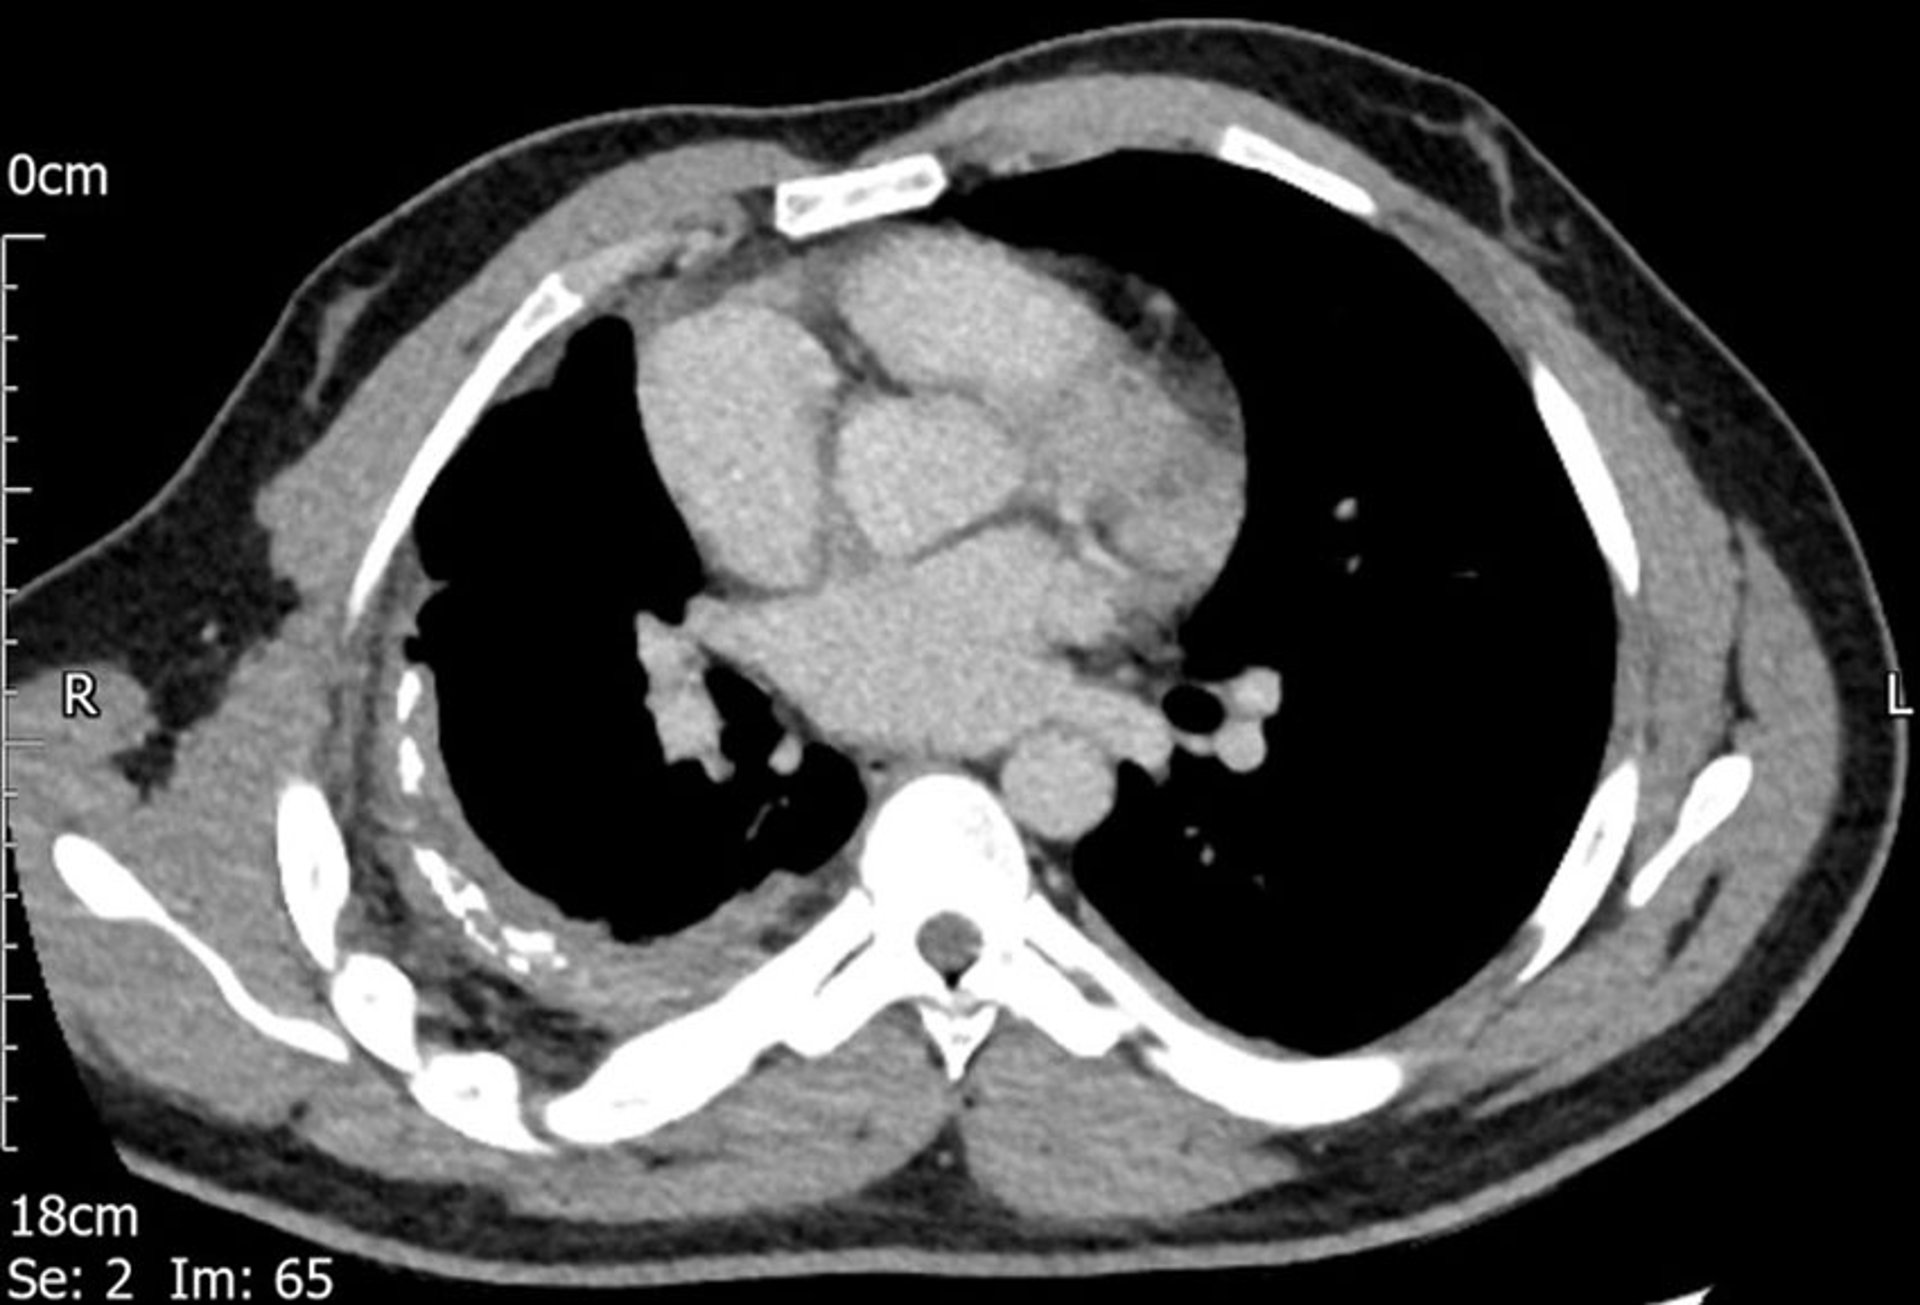

Pleural thickening is seen on the right in this CT scan.

Image courtesy of Najib M. Rahman, BMBCh MA (oxon) DPhil.